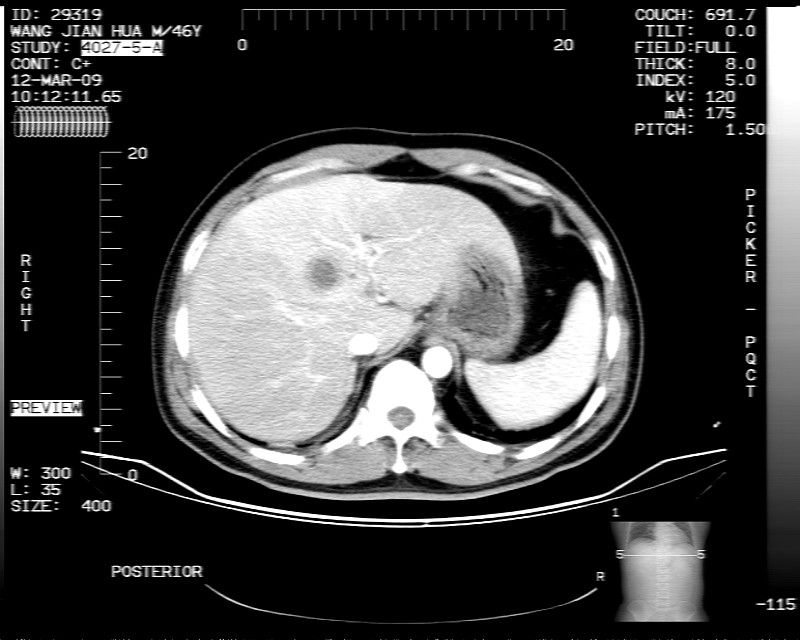

男性,52岁,腹痛,无发热,生化检查无明显异常,既往有胰腺炎病史,经治疗好转出院。

胆囊炎,肝脓肿(周围可见异常灌注)

1)考虑肝左叶内侧段肝脓肿,不排除转移瘤。2)脂肪肝。3)慢性胆囊炎。4)十二指肠降部肿瘤可能。

胆囊炎、脂肪肝、肝脓肿。